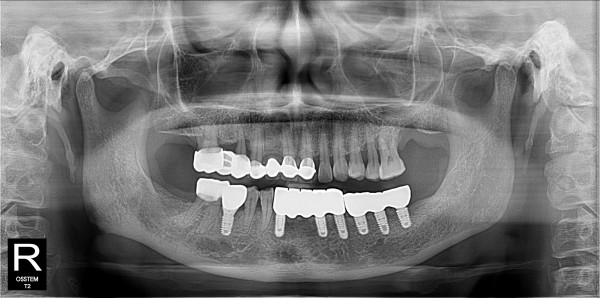

하악 틀니에서 네이게이션 임플란트